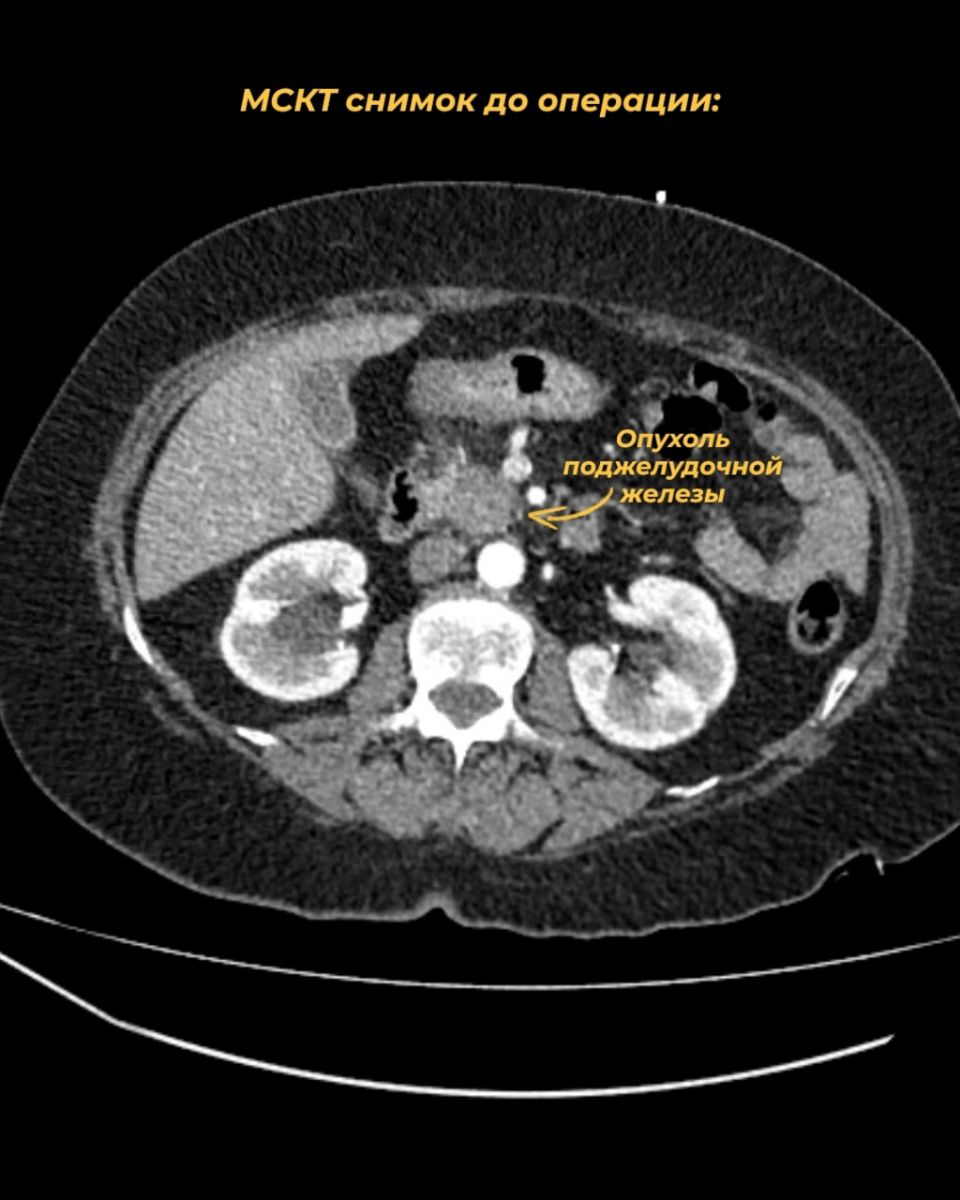

Параллельно с лечением в Ивановском онкодиспансере женщина обратилась за вторым мнением в одну из столичных клиник, где опухоль была признана неоперабельной и рекомендовали химиотерапию. Однако ивановские хирурги, основываясь на собственном опыте и мировой статистике, пришли к выводу о возможности радикального хирургического вмешательства. После повторного КТ и тщательного анализа с 3D-реконструкцией сосудов они предложили пациентке операцию.